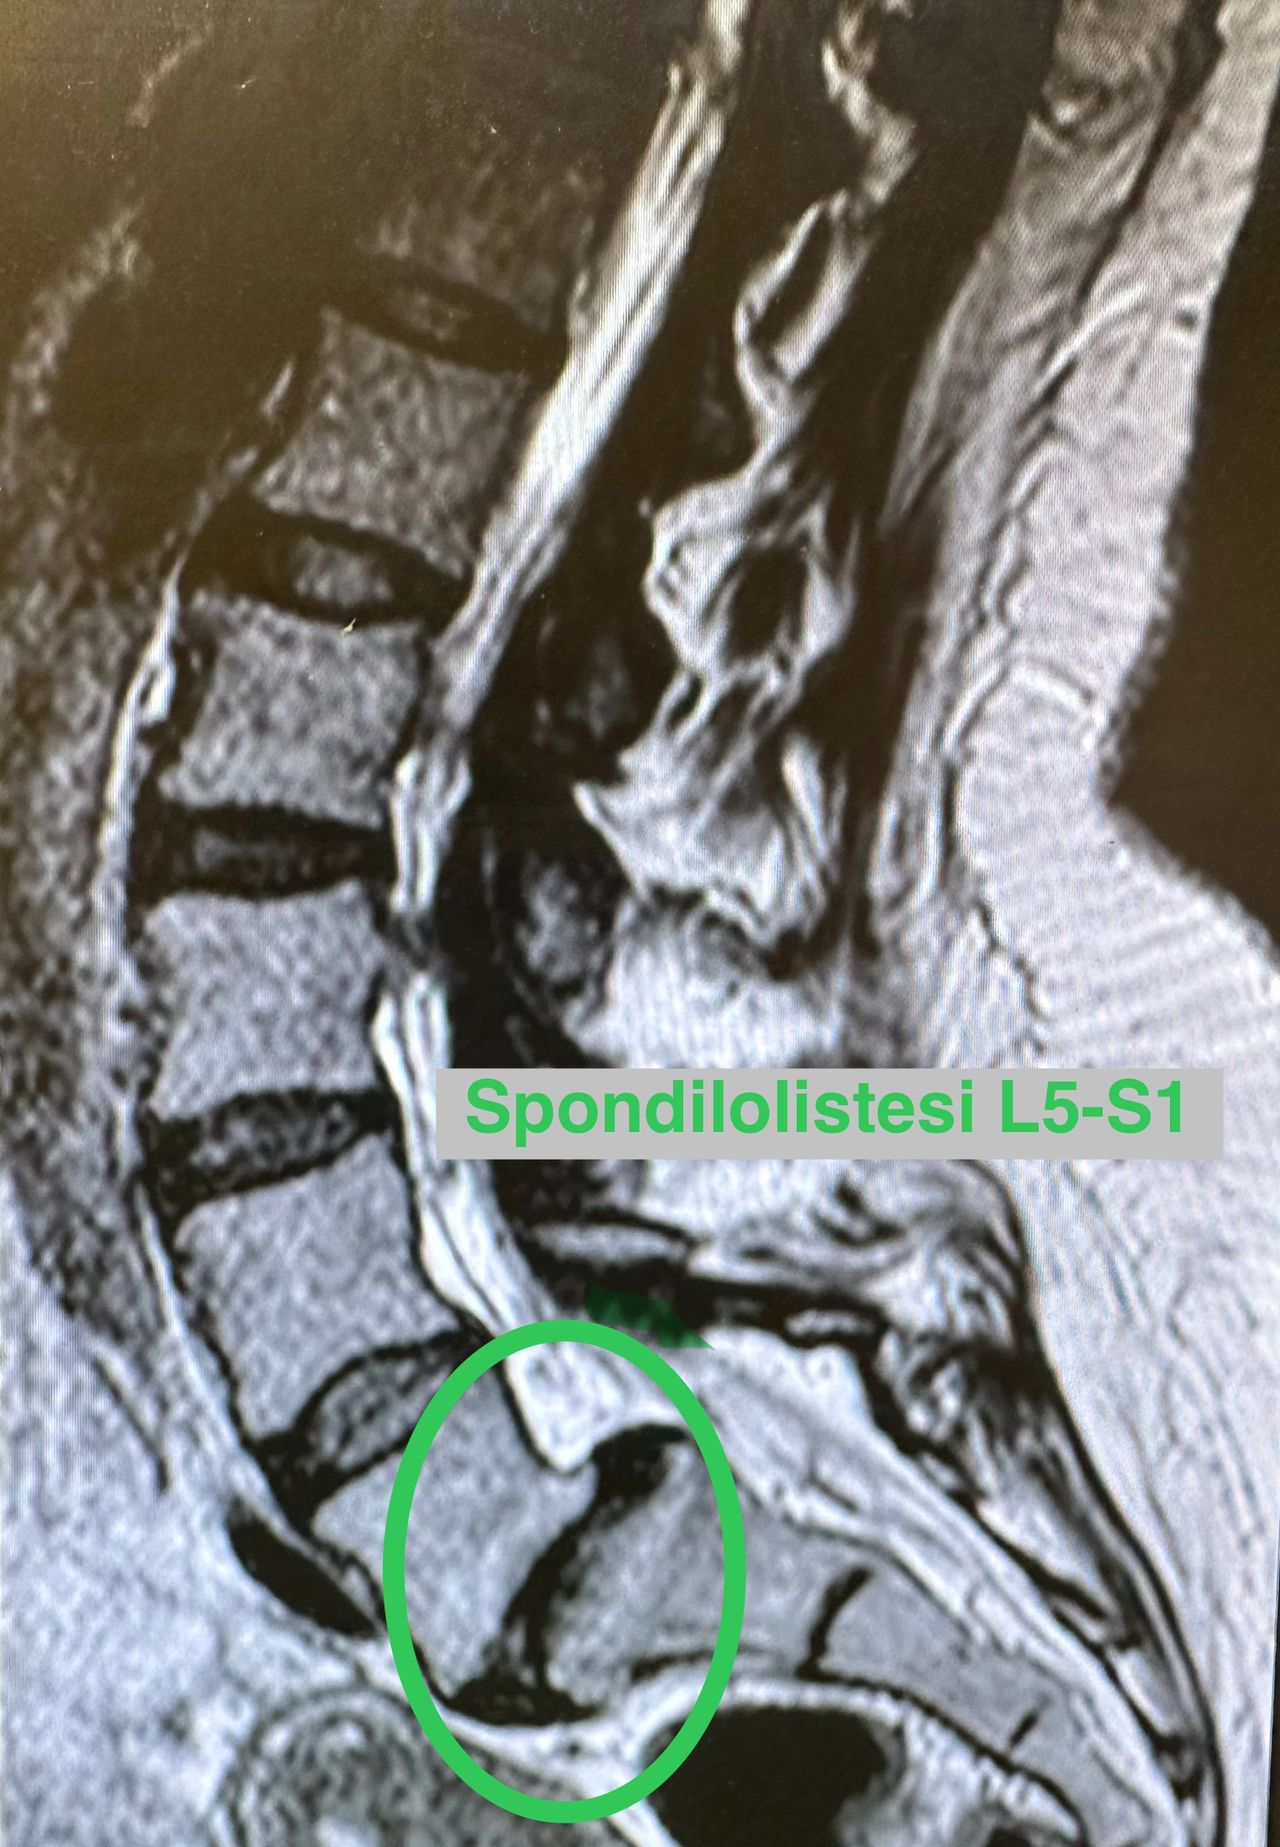

- Chirurgia Mininvasiva percutanea vertebrale - stabilizzazioni e artrodesi intersomatiche (per fratture vertebrali, spondilolistesi, instabilità vertebrali, discopatie)

Mi ha operato lunedì a livello L5-S1 con un intervento di stabilizzazione e discectomia, dopo aver provato di tutto senza ottenere alcun beneficio. Fin dal primo momento mi sono sentita seguita con grande professionalità e umanità.